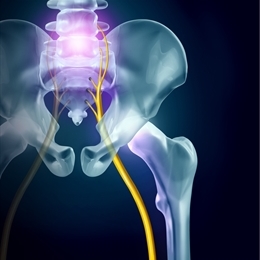

Siyatik Nedir Belirtileri Nedenleri Ve Tedavisi Medicana

Sinir Sikismasi Tedavisi Belirtileri Ve Ameliyati Medicana Saglik Grubu